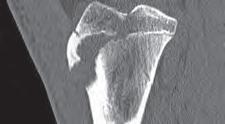

Podział złamań kości rosnących, tzw. złamań nasadowych: A – schematyczne przedstawienie klasyfikacji złamań; B – SH I (RTG, widok z przodu i z boku); C – SH II (RTG, widok z przodu i z boku); D – SH II (TK, widok z boku); E – SH III (RTG, widok z przodu i z boku); F – SH IV (RTG, widok z przodu i z boku); G – SH V (RTG, widok z przodu i z boku).

Rozpoznanie

Objawy złamania to silny ból uniemożliwiający stanie i chodzenie, zniekształcenie obrysów stawu kolanowego przez krwiak i różnego stopnia przemieszczenie nasady kości piszczelowej. Należy dokładnie zbadać stan ukrwienia i unaczynienia kończyny pod kątem objawów uszkodzenia tętnicy podkolanowej i nerwu strzałkowego. Trzeba ocenić bolesność uciskową oraz napięcie w przedziałach powięziowych podudzia: przednim, bocznym, tylnym powierzchownym i tylnym głębokim. U pacjentów z podejrzeniem wzmożonego ciśnienia wewnątrzprzedziałowego należy wielokrotnie powtarzać badanie ukrwienia i unerwienia kończyny, a w razie zaistnienia wskazań wykonać bezpośredni pomiar ciśnienia w przedziałach. Powinno się zawsze podejrzewać możliwość uszkodzeń więzadłowych współistniejących ze złamaniem. Badania obrazowe to RTG w pozycji AP, bocznej i skośnej. Wykonanie badania TK może być konieczne w celu pełnej oceny rozległości

złamania. W przypadku podejrzenia uszkodzenia tętnicy podkolanowej należy wykonać angio-TK lub arteriografię.

Leczenie złamania bliższej nasady piszczeli w przypadku uszkodzenia typu 1 i 2 według Saltera i Harrisa leczymy nieoperacyjnie. Należy wykonać zamkniętą repozycję i unieruchomić w opatrunku gipsowym udowym w zgięciu kolana 30–60°, zapewniającym najlepszą stabilność odłamów. Okres unieruchomienia wynosi od 6 do 7 tygodni. Po tym czasie usuwamy gips i zaczynamy ćwiczenia zwiększające zakres ruchomości stawu kolanowego oraz wzmacniające siłę mięśnia czworogłowego. Ważne jest, by prowadzić częste kontrole stanu ukrwienia i unaczynienia oraz kontrole radiologiczne w celu wykrycia ewentualnych przemieszczeń odłamów. Złamania pierwotnie niestabilne lub wtórnie przemieszczone wymagają zamkniętej repozycji stabilizacji drutami K. Typ 3 i 4

Złamania rzepki i podudzia

złamania według Saltera i Harrisa wymaga leczenia operacyjnego w postaci otwartej repozycji i stabilizacji śrubami. Należy unikać krzyżowania metalu zespalającego z chrząstką wzrostową. Kończynę zgiętą w kolanie do 30° unieruchamia się w gipsie udowym na okres 6–8 tygodni. Po tym czasie rozpoczynamy ćwiczenia czynne poprawiające zakres ruchomości kończyny.